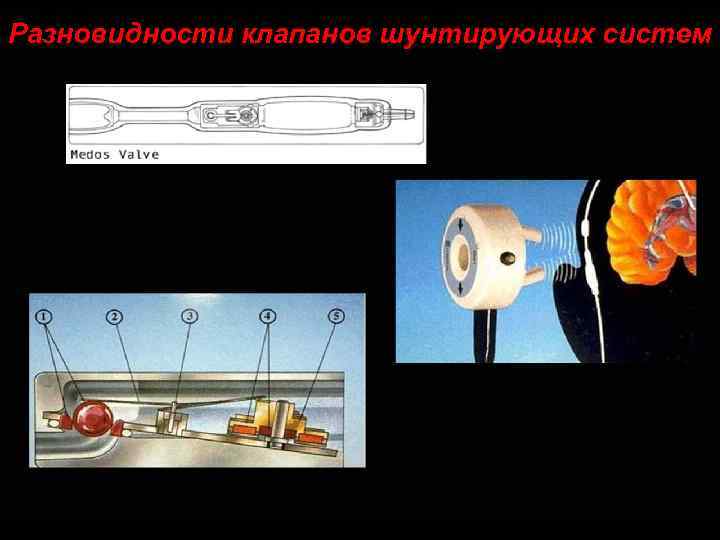

Разновидности клапанов шунтирующих систем 102